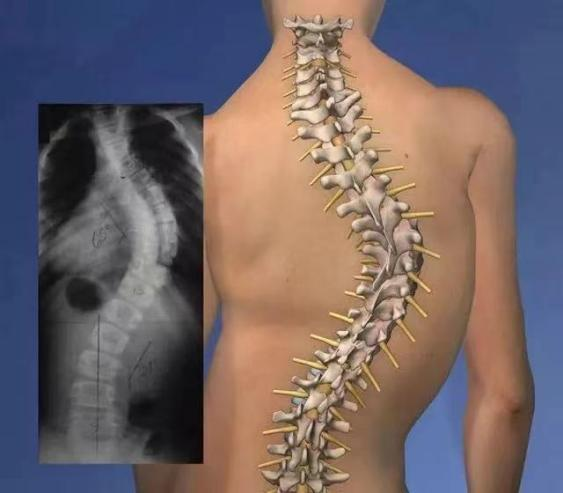

病理定义

脊柱侧弯指脊柱偏离中线形成>10°的C型/S型三维畸形。青少年特发性脊柱侧弯(AIS)占临床病例75%以上,高发于10岁至骨成熟期人群:

脊柱侧弯早期,没有明显症状,也看不出明显的躯体畸形,因此常常被忽略。一旦青少年患者进入生长发育时期,脊柱侧弯角度越大,进展就越快,因早期未及时干预,而错过最佳矫治时机。